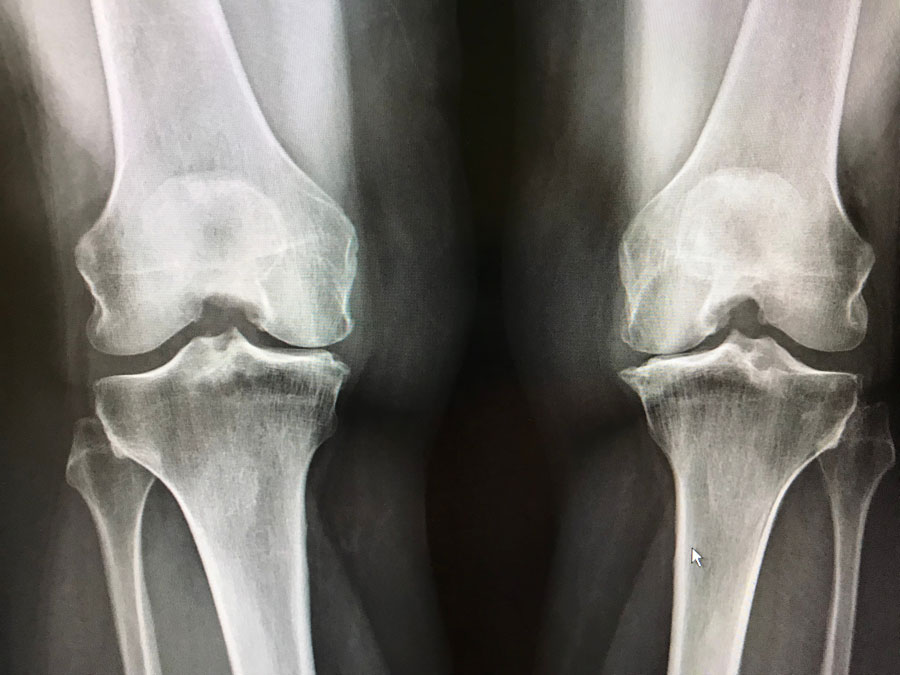

Utilización de la atención médica y mortalidad en personas con artrosis en el Reino Unido

Las personas con osteoartrosis tuvieron mayores tasas de consultas de médicos de cabecera, ingresos hospitalarios y mortalidad por todas las causas que variaron entre los sitios conjuntos. Br J Gen Pract,, 10 de julio de 2023